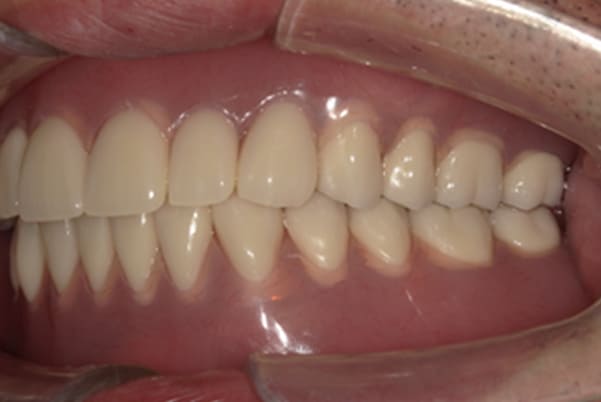

治療前は上下奥歯の入れ歯が削れていることで、かみ合わせが低くなり唇もつむった状態でした。

かみ合わせを適切な高さに戻したことで、本来の自然な口元へ。